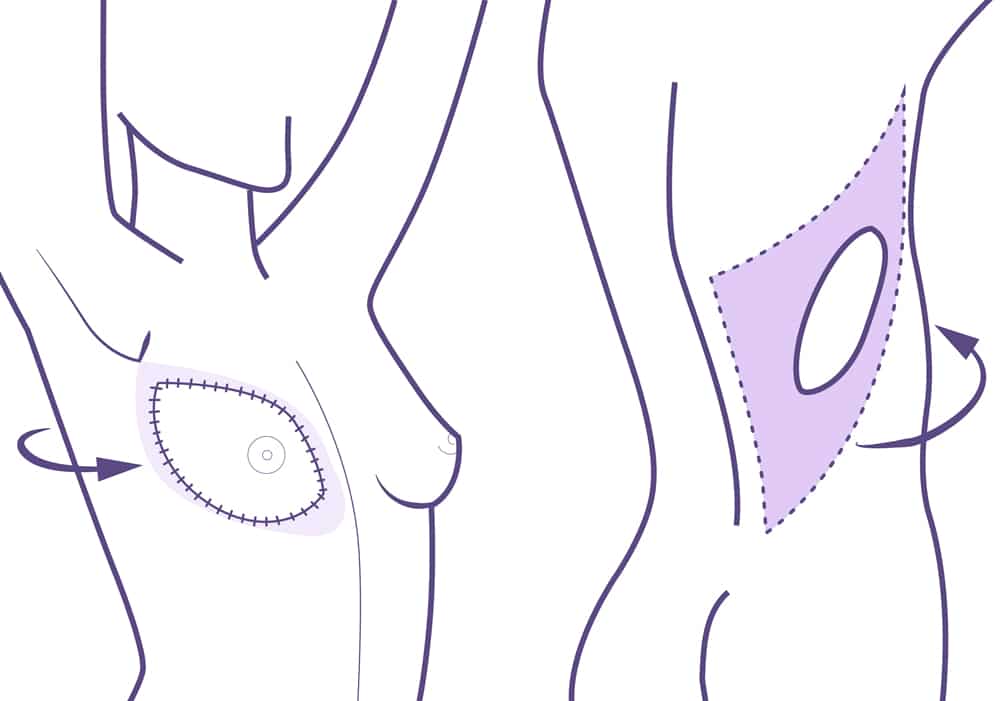

Consiste en la movilización o el trasplante de tejidos de otras zonas del cuerpo como el abdomen, la espalda o las nalgas.

En algunos casos estos tejidos siguen unidos a su sitio original, conservando su vascularización, y son trasladados hacia la mama mediante un túnel que corre por debajo de la piel.

En otros casos son separados completamente de su sitio original y son trasplantados al pecho mediante la conexión a los vasos sanguíneos de esta zona.

Esta técnica es más compleja, deja más cicatriz y el período de recuperación es mayor. Sin embargo, el resultado estético es mucho más natural. Esta operación se realiza bajo anestesia general con una estancia hospitalaria de 3 días.